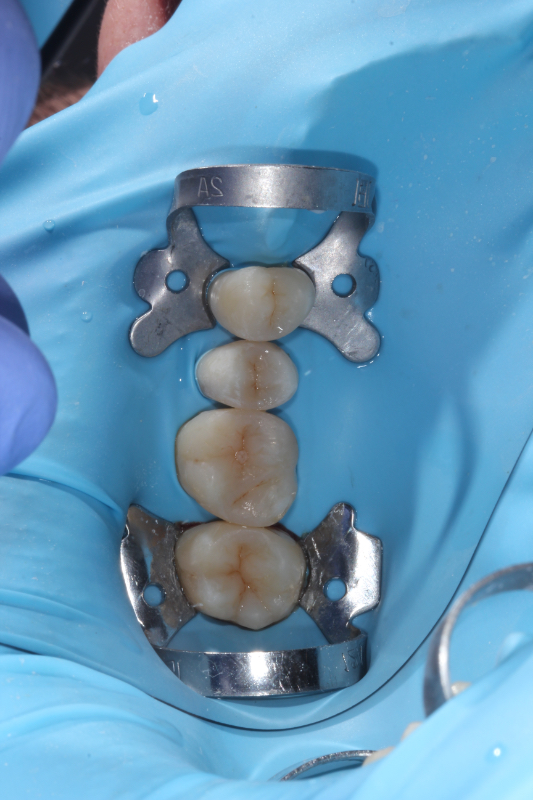

- Zaplnění kanálků — hermetické utěsnění speciálním materiálem.

- Obnova zubu — výplň nebo korunka, aby byl zub opět pevný.

Po endodontickém ošetření je důležité zub správně definitivně obnovit (např. onlay, korunkou), aby dlouhodobě vydržel, a pokračovat v běžné ústní hygieně.